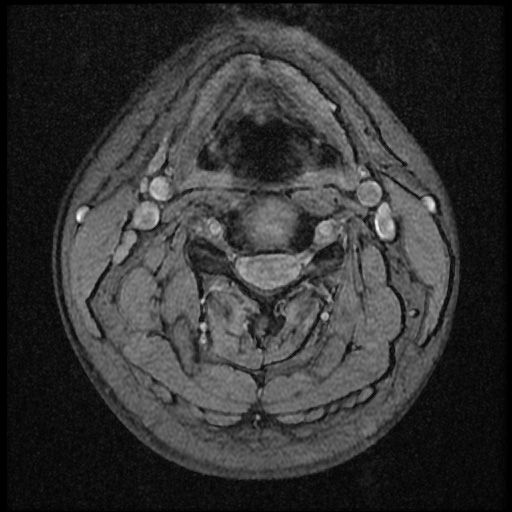

이 MRI 사진은 21년도 사고 당시 찍은 MRI 사진 입니다. 확인 부탁드립니다~

전체 mri를 다 봐여겠지만 보여주신 mri 컷에서는 의미있는 경추 디스크탈출이 보이지 않습니다.